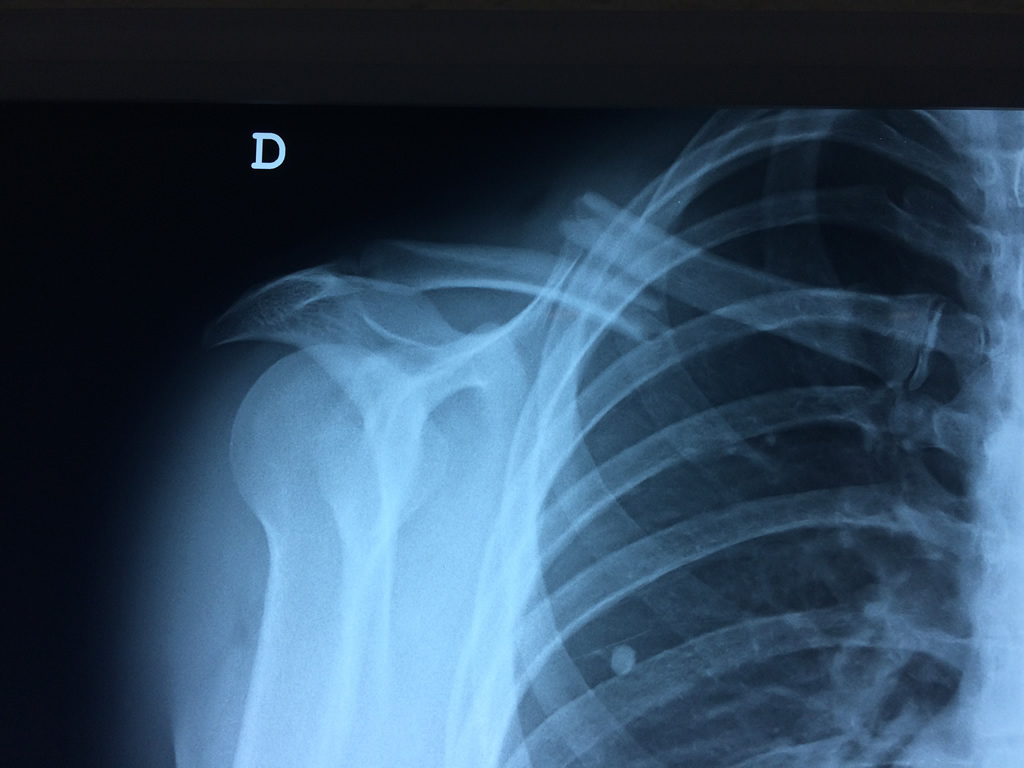

Cirugías de Húmero - Clavícula